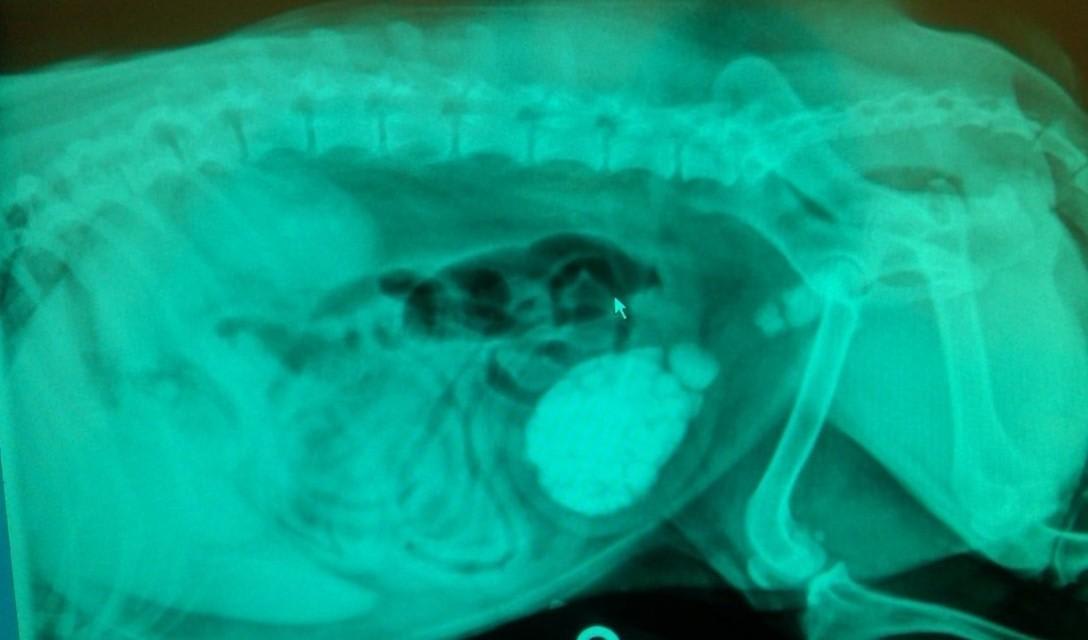

Some stones are noted during palpation of the abdomen during a routine physical exam. In other cases, the diagnosis of bladder stones in dogs is made or confirmed with abdominal x-rays or ultrasound of the bladder. Most stones are radiopaque, meaning they show up on the radiographic film as obvious white objects within the urinary bladder. A few are radiolucent and they do not show up on x-rays. Radiolucent stones may require diagnosis using a contrast dye and x-ray or ultrasound.